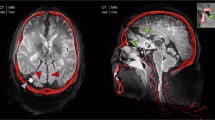

Furthermore, in all three cases with craniocerebral gunshot injuries, a dark (hypo intense) zone could be delineated adjacent to the wound tract in the region of the diencephalon and mesencephalon on 7 T MRI, which was hardly detectable on 3 T MRI and was not observed in the control case (Fig. 7). In all three cases, the dark zones were significantly larger on 7 T MRI than on 3 T MRI according to ROI measurements (case 1: p = 0.001; case 2: p = 0.002; case 3: p = 0.030).

Comparison of the control case (a and b) with case 1 (c and d) and case 2 (e and f) in terms of the extent of cavitation injuries delineated by a dark/hypo intense zone (red circle) beyond the wound tract (arrowhead) on 7 T MRI (upper row) and on 3 T MRI (lower row). The dark/hypo intense zone was defined as damaged tissue. On 7 T MRI (c and e), the damaged tissue beyond the wound tract could be highlighted